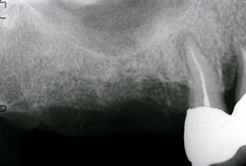

数ヶ月後上部構造を作成して治療終了。

- インプラント(2本)

- 上顎洞内の骨造成 (サイナスリフト)

- インプラント上部金合金前装冠 (2本)